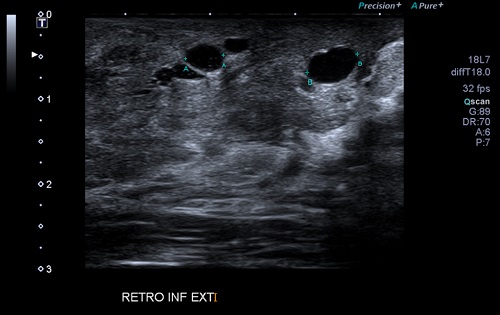

Ante estos hallazgos, se solicita una ecografía de mama, realizada en el hospital de referencia a las 2 semanas de la valoración. En el informe de radiología informan a nivel de la región retroareolar 6 quistes de pequeño tamaño, el mayor de 6,3 mm, de aspecto no complicado; hallazgos compatibles con la obstrucción de la glándula de Montgomery (Fig. 1).

| Figura 1. Ecografía de mama: pequeños quistes localizados en la región retroareolar del cuadrante inferoexterno de la mama derecha, el mayor de 6,3 mm de diámetro transverso |